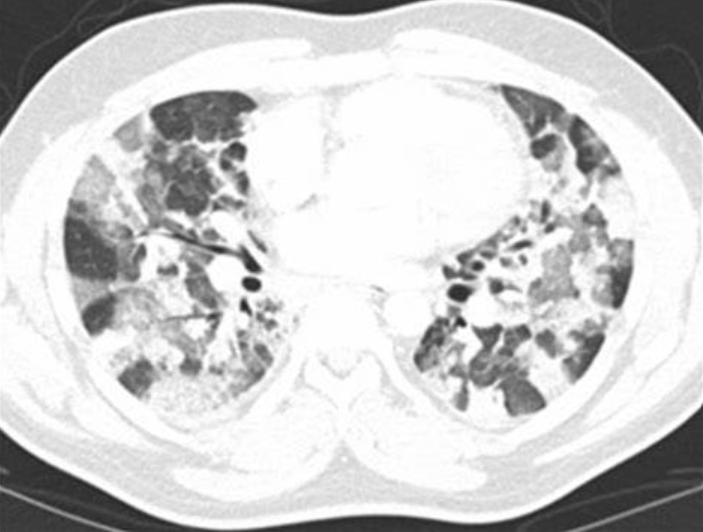

Head cheese sign sarcoidosis

Head cheese sign sarcoidosis-• The head cheese sign refers to a juxtaposition of regions with ground glass opacities, mosaic attenuation pattern, and normal lung tissue This sign is highly specific for hypersensitivity pneumonitis, although it can also be seen in other mixed infiltrative and obstructive processes • Several other metaphoric chest CT scan signs have been described linking abnormal imagingDiscussão de caso clínico

The head cheese sign refers to a juxtaposition of regions with three (or sometimes more) different densities/regions of different attenuation within the lungs groundglass opacities (high attenuation) mosaic attenuation pattern (low attenuatioThe head cheese sign refers to a juxtaposition of regions with three (or sometimes more) different densities/regions of different attenuation within the lungs HEAD CHEESE SIGN, GROUND GLASS, MOSAIC PATTERN SARCOIDOSIS, STAGE IV, PTX, ENCASEMENT · The name of this sign is derived from "headcheese" which is a European dish consisting of meat pieces The name indicates the heterogeneous mosaic appearance of thorax This occurs due to infiltration of inflammatory cells in parenchyma (ground glass opacity) in a patchy distribution with normal lung in between There is also a bronchospastic component of

May 10, 15 This Pin was discovered by Dr Nazahat Pasha Discover (and save!) your own Pins onThe head cheese sign is considered to be highly specific for hypersensitivity pneumonitis, although it can also be seen in other mixed infiltrative and obstructive processes (eg sarcoidosis and atypical infections associated with bronchiolitis (eg mycoplasma pneumonia) Head cheese, believe it or not, is not cheese and is often not made of the head It is, in fact, a type of terrine,Corpus ID Headcheese Sign A Useful Radiological Marker @article{Sarkar17HeadcheeseSA, title={Headcheese Sign A Useful Radiological Marker}, author={Rathindranath Sarkar and R Paul and R Pandey and I Thakur and A Karmakar}, journal={The Journal of the Association of Physicians of India}, year={17}, volume={65 4},

The head cheese sign refers to a juxtaposition of regions with three (or sometimes more) different densities/regions of different attenuation within the lungs groundglass opacities (high attenuation) mosaic attenuation pattern (low attenuation) normal lung tissue (normal attenuation)Developed by renowned radiologists in each specialty, STATdx provides comprehensive decision support you can rely on Head Cheese Sign link Bookmarks (0) Chest Diagnosis Overview of Chest Imaging Chest Radiographic and CT Signs Head Cheese SignCurrent usage Wisconsin is associated with cheese because the state historically produced more dairy products than other American states, giving it the nickname "America's Dairyland" The use of the term "cheesehead" as a derogatory word for Wisconsinites originated with Illinois football and baseball fans to refer to opposing Wisconsin sports fans The term, however, was quickly

Information and translations of headcheese in the most comprehensive dictionary definitions resource on the web · Headcheese Sign Headcheese sign refers to a radiological pattern in a chest CT scan that can be associated with several pathological entities, from different etiology such as an infection, an immune response or drugs The name comes from the juxtaposition of 3 different densities with welldefined margination of hazy groundglass opacity that looks like a "paté" TheDefinition of headcheese in the Definitionsnet dictionary Meaning of headcheese What does headcheese mean?